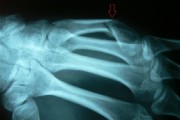

Fracture of the fifth metacarpal bone.

This young man fell off the skateboard and broke his fifth metacarpal. The conducted cast immobilization in the emergency hospital was found to be ineffective, because the bone was flexed too much.

After the straightening and plating the injury healed very well.